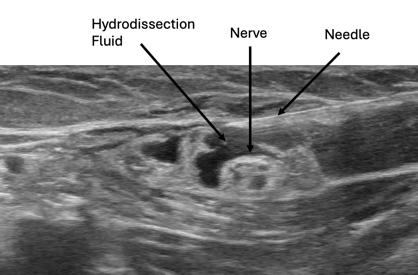

The hydrodissection technique uses fluid and gentle pressure to widen soft-tissue spaces, freeing the nerve and giving it room to breathe. Various fluids can be used for hydrodissection, including dextrose prolotherapy and PRP. Prolotherapy solutions have been shown to reduce pain and swelling in the carpal tunnel more effectively than steroids. PRP also shows good success, especially when growth factors are needed to “jump-start” the functions of a damaged nerve. Research has demonstrated that PRP may have advantages over prolotherapy and steroid injections, especially when there is significant nerve dysfunction. The image below shows how hydrodissection fluid can free the nerve from surrounding soft connective tissue. This technique can also be effective in areas with surgical scar tissue that entraps the nerve.